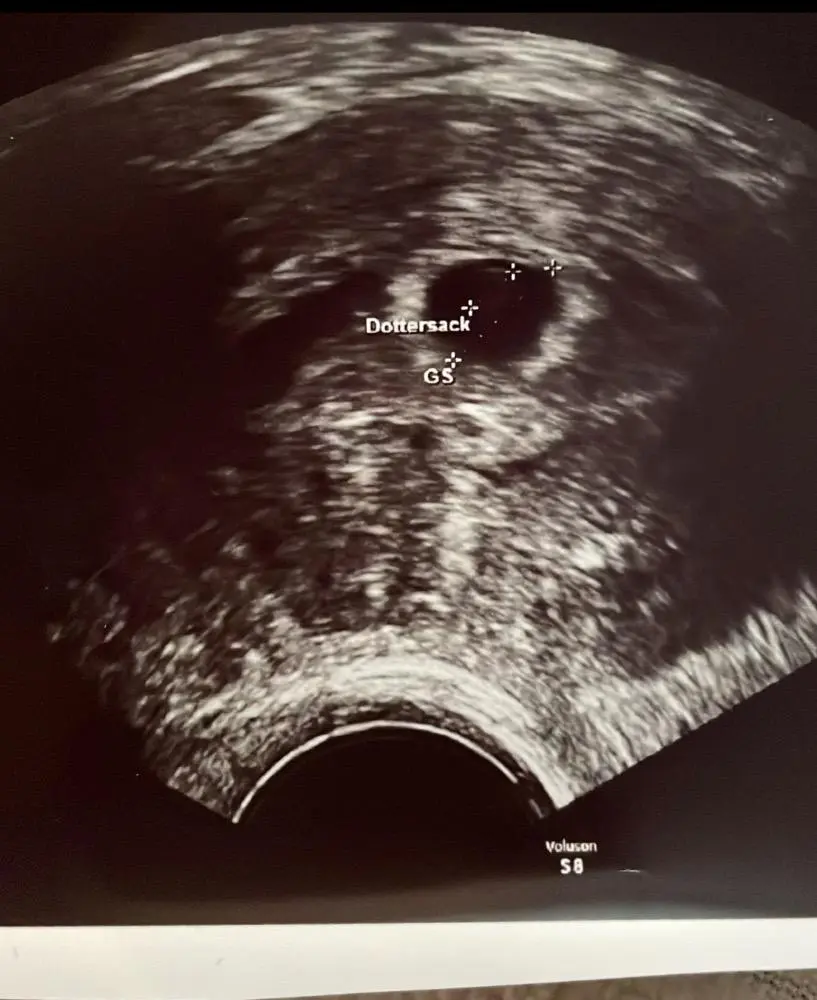

Diagnose eines retrochorialen Hämatoms

Ein retrochoriales Hämatom kann durch eine Ultraschalluntersuchung diagnostiziert werden. Der Ultraschall kann die Größe und Lage des Hämatoms zeigen. In einigen Fällen kann eine Blutuntersuchung erforderlich sein, um andere Ursachen für die Blutungen auszuschließen.